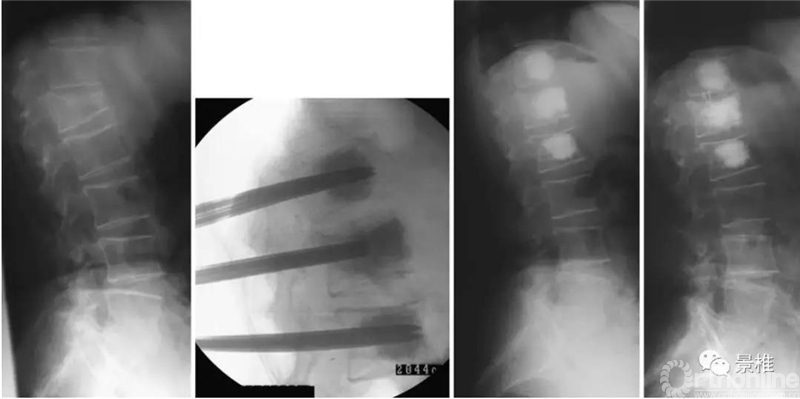

现在伤椎和上下邻椎均做骨水泥通道,邻椎注入骨水泥。并插入内芯超出套杆尖端5mm,使骨水泥充分挤出(原文用骨穿刺活检通道套杆,和椎体成形通道应该差不多粗细)。

上下邻椎套杆相交加压,撬拨复位伤椎高度及前凸序列,伤椎注入骨水泥。

该技术可以恢复大约15°的椎体后凸和10°的整体节段后凸。邻椎骨水泥注入还预防邻椎骨折。

此法既节省了球囊费用,又通过撬拨复位技术达到PKP效果。